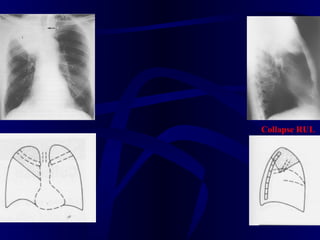

Collapse RUL

Rul collapse